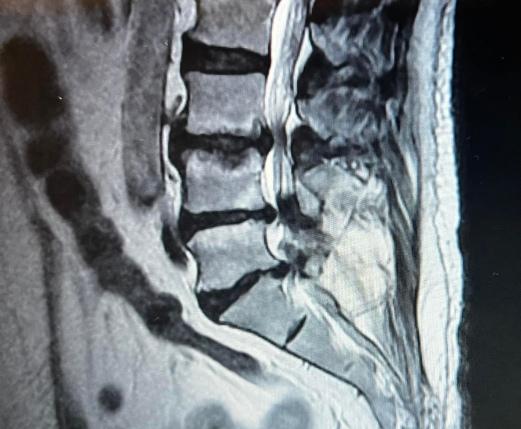

● Hernia de disco

● Tumores cerebrales, de médula espinal y columna vertebral.

● Cervicalgia, lumbalgia, ciatalgia

● Mielopatías

● Radiculopatía

Especialistaencirugíade columnavertebral

• MICROCIRUGÍA DE HERNIA DE DISCO

• CIRUGÍA DE HERNIA DISCAL CERVICAL

• DISCO ROTO

• CIÁTICA